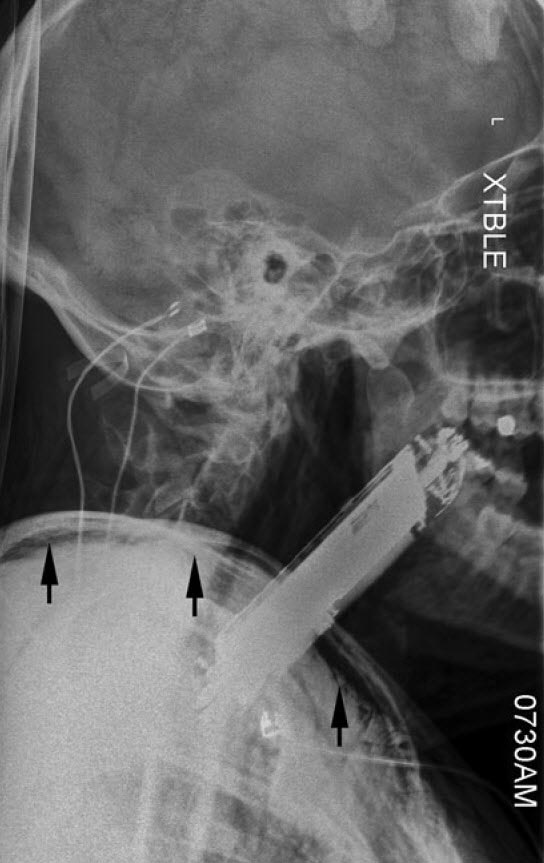

یک پزشک - مرد ۳۵ ساله‌ای بدون مشکل قبلی پزشکی، به اورژانس آمد، او بعد از مصرف ماده روانگردان فن‌سیکلیدین یا PCP دچار توهمات شنوایی دستوری شده بود.

تحت تأثیر این توهم‌ها، او گوشی هوشمند خود را که ابعادش ۴ در ۸ سانتیمتر بود، بلعیده بود!

در بدو ورود او آشفته، اما هوشیار بود، بزاقش جاری بود و تنگی نفس (دیسترس) در حد متوسط داشت.

گوشی موبایل به وضوح وارد حلق (اوروفارنکس) او شده بود و این قسمت را به جلو منحرف کرده بود. سرعت تنفس او بالا رفته بود و در هر دقیقه به ۲۴ تنفس رسیده بود. میزان اشباع اکسیژن او ۹۲ درصد بود و سرعت ضربان قلب‌اش ۱۳۱ ضربه در دقیقه بود، فشار خونش هم ۱۳۷ روی ۶۴ میلیمتر جیوه بود.

پزشکان اورژانس تلاش کردند تا با فورسپس مگیل Magill گوشی را خارج کردند، اما ناموفق بودند.

بعد از همه اینها پزشکان متوجه شدند که نوموتوراکس دوطرفه و آمفیزم زیر پوستی در گردن و اندام فوقانی دارد.

یعنی هوا وارد حفره جنب او شده بود، در این شرایط هوایی که به صورت غیرطبیعی در حفره جنب جمع می‌شود به ریه‌ها فشار می‌آورد و باعث می‌شود ریه‌های نتوانند به صورت طبیعی از هوا پر شوند، حتی امکان دارد، این فشار باعث اختلال در ورود و خروج خون به قلب شود که بسیار خطرناک است.

تشخیص این بود که ورود جسم خارجی باعث پاره شدن فارنکس در قسمت پشتی شده است.

سی تی اسکن درخواست شد و تشخیص را تأیید کرد، همچینن سی تی نشان داد که هوا در قسمت میانی قفسه سینه (مدیاستن) جمع شده است.